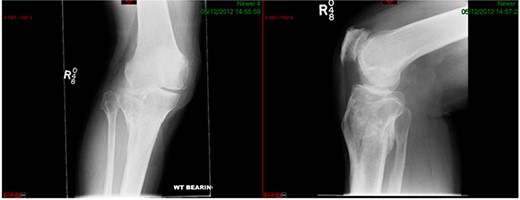

CASE 1

A 68-year-old gentleman who was diagnosed with a Schatzker type VI fracture having fallen 3 m from a ladder (Figs 1 and 2). The injury was closed and neurovascularly intact. The patient was monitored for signs of compartment syndrome. He rapidly developed significant fracture blisters that persisted for over 2 weeks despite regular dressing care. He was deemed too high risk for acute operative intervention because of a high risk of wound complications. Following a multidisciplinary team discussion, he was managed in a cast then a knee brace, mobilising non weight bearing for 12 weeks, at which point the fracture was seen to be healing in a valgus malalignment. The patient was allowed to partially weight bear and received physiotherapy. He was reviewed regularly until fracture had united (Fig. 3). At 8 months post-injury, the patient underwent total knee arthroplasty utilizing a Depuy Synthes (Warsaw, In) PFC Sigma TC3 tibial metaphyseal sleeve and stem, and femoral component without sleeve or stem (Fig. 4). The patient was reviewed post-operatively in clinic at 6 months, the wound had fully healed and the range of motion was 0°–120°. The patient’s pain was significantly reduced, and they were independently mobile. They were kept under annual review and seen at 5 years post-operatively with an Oxford Knee score of 35; the patient used no walking aids and was pain free at rest or during normal walking, with the radiograph demonstrating good osseointegration. The latest follow-up at 8 years revealed no radiographical change in implant (Fig. 5).